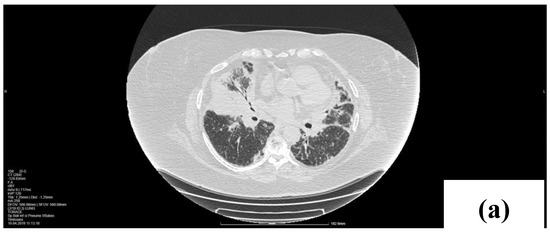

2. Case Presentation

2.1. Laboratory, Radiological, and Histological Examinations

2.2. Treatment and Outcome